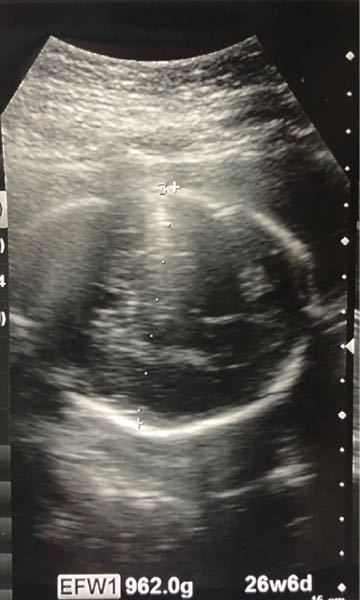

ただいま 2人目を妊娠中です 7ヶ月です このエコー写真は女の子か男の子か Yahoo 知恵袋

妊娠7ヶ月 エコー写真でここまで分かる ついに性別判明 25歳はじめての妊娠 8 18年3月21日 ウーマンエキサイト 1 2

妊娠7ヶ月です おまたの下から撮ったエコーです 男の子か女の子か 妊娠 教えて Goo